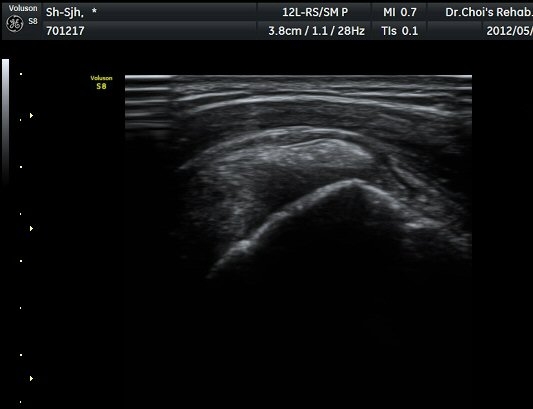

µÈ´Ù(»çÁø 3). ±Ø»ó°Ç Á¾´Ü¸é°Ë»ç»ó ±Ø»ó°Ç ºÎÂøºÎ¿¡ °í¿¡ÄÚ µ¢¾î¸®°¡ °üÂûµÇ°í(»çÁø 4, 5)

ÆÄ¿öµµÇ÷¯ °Ë»ç¿¡¼­ Ç÷·ùÁõ°¡¸¦ º¸ÀδÙ(»çÁø 6).  Ⱦ´Ü¸é°Ë»ç¿¡¼­µµ °í¿¡ÄÚ µ¢¾î¸®¿Í

Ç÷·ùÁõ°¡°¡ È®ÀεȴÙ(»çÁø 7, 8).